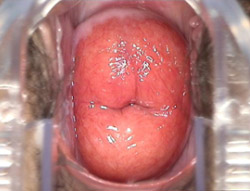

宫颈糜烂

中度宫颈糜烂